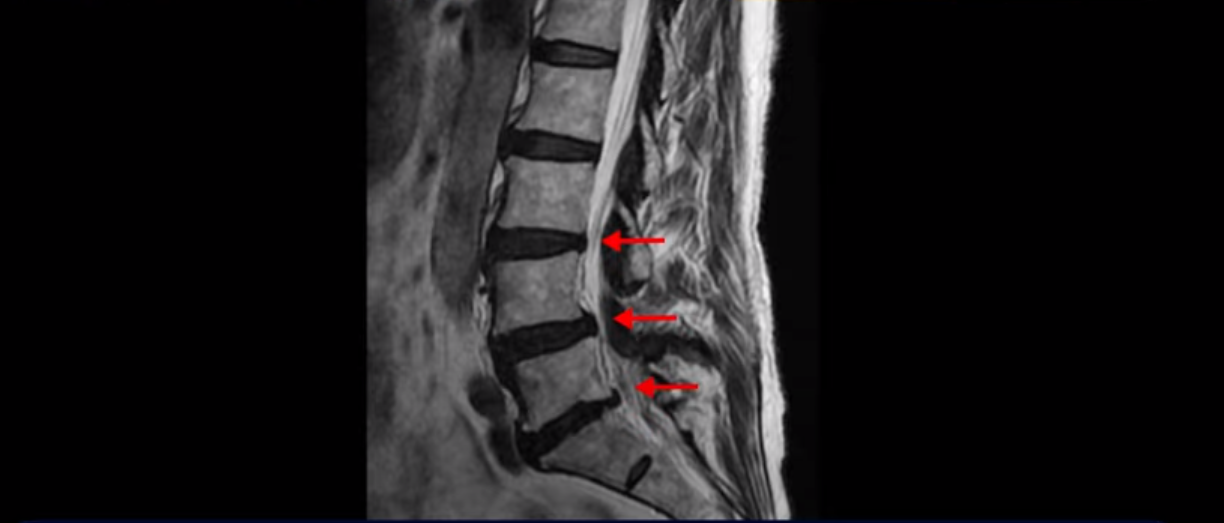

이분 MRI 보면서 설명드린 후 왜 이분처럼 발병한지 얼마 안된 협착증이 치료가 정말 빠르고 쉬운 건지 또 치료는 어떻게 하는 건지 자세히 설명 드리도록 하겠습니다.

MRI를 보면 척추 여러 마디가 퇴행되어 있고

척추관도 좁아져 있고

특히 왼쪽 신경가지가 빠져나가는 4번 5번, 5번 1번 추간공들이 많이 좁아져 있습니다.

그래서 이분은 몇 달 전부터 갑자기 왼쪽 엉덩이부터 발바닥까지 저리고 아픈 증상이 생겨서 걷기도 어렵고 무릎도 차고 시립니다. 그런데 왜 이렇게 얼마 전에 갑자기 발병한 협착증일수록 치료가 정말 빠르고 쉽다는 걸까요?